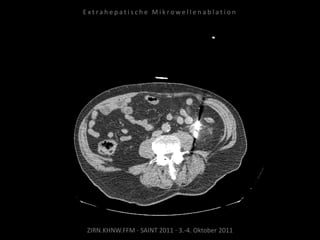

Verlaufskontrolle:

CT 21.10.2010

MRT 21.01.2011

MRT 08.04.2011

Zunehmende Tumoraktivität der

Metastase kaudal der linken Niere

ohne signifikante Größenzunahme.